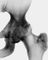

Еще одним последствием поражения суставных хрящей являются очаговые дистрофические и некротические процессы в субхондральной губчатой кости, соответствующие локальным пикам механических напряжений. В результате этих процессов формируются кистовидные образования. Последние наиболее характерны для коксартроза, при котором они часто множественны и достигают больших размеров (рис. 1). При субхондральном расположении кистевидных образований могут наблюдаться переломы их стенок и «вскрытие» в полость сустава. Другой механизм развития кистевидных образований — нагнетание под давлением синовиальной жидкости через трещины суставного хряща и замыкающих пластинок суставных поверхностей в субхондральные костномозговые пространства (внутрикостные ганглии). По этому типу обычно развиваются одиночные крупные кистовидные образования, в тех случаях, когда они представляют собой наиболее яркое проявление остеоартроза.

Рентгенологическая семиотика остеоартроза складывается из признаков, отражающих дистрофические изменения в суставных хрящах (сужение суставной щели) и в костной ткани (уплощение и деформация суставных поверхностей, кистевидные образования), нестабильность суставов (подвывихи, искривления оси конечностей), реактивные компенсаторно-приспособительные процессы (краевые костные разрастания, субхондральный остеосклероз).

Хотя остеоартроз начинается с поражения суставных хрящей, его наиболее ранним рентгенологическим симптомом обычно служат краевые костные разрастания как следствие активной пролиферации периферических отделов суставного хряща. Они проявляются вначале заострением краев суставных поверхностей, а затем, нарастая, образуют массивные костные шипы и губы. Краевые остеофиты, как правило, раньше обнаруживаются со стороны суставных впадин.

Сужение суставной щели свидетельствует уже о значительных изменениях суставных хрящей. Суставная щель может стать клиновидной, суживаясь с одной стороны и нередко расширяясь при этом с противоположной, что указывает на недостаточность связочного аппарата и нестабильность сустава. При остеоартрозе не возникает костных анкилозов и всегда сохраняется хотя бы еле заметная суставная щель.

Параллельно сужению суставной щели утрачивается амортизационная функция суставных хрящей, предохраняющих подлежащую костную ткань от механических перегрузок. В качестве защитного механизма развивается остеосклероз субхондральной губчатой кости. Он особенно выражен при коксартрозе в крыше вертлужной впадины, распространяясь иногда почти на все тело подвздошной кости. Однако рано или поздно этот механизм компенсации становится недостаточным. Механические силы, передающиеся непосредственно с одной суставной поверхности на другую, вызывают атрофию от давления их наиболее нагружаемых участков и прежде всего центральных отделов суставных головок. Вследствие этого они уплощаются и одновременно расширяются.

В нашей стране распространена рентгенологическая классификация остеоартроза по стадиям развития, разработанная Н.С. Косинской. Остеоартроз в I стадии характеризуется главным образом краевыми костными разрастаниями при незначительном сужении суставной щели. Во II стадии она сужена более отчетливо, возникает субхондральный остеосклероз. Резкое сужение суставной щели в III стадии О. сопровождается уплощением суставных поверхностей и развитием кистевидных образований. Следует отметить, что наиболее ранние морфологические изменения при остеоартрозе на рентгенограммах не определяются (так называемая рентгенонегативная стация).